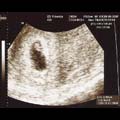

• 7. tjedan

Vaše djetešce je veliko kao zrno riže. Prava ljudina!